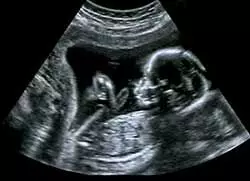

Nagpur News: रैकेट का पर्दाफाश - सोनोग्राफी सेंटर सील, 2 डॉक्टरों के खिलाफ दर्ज हुआ मामला

Nagpur News. शहर में अवैध गर्भलिंग परीक्षण करने वाले रैकेट पर मनपा के स्वास्थ्य विभाग ने शिकंजा कसा। बेहद गोपनीय और योजनाबद्ध स्टिंग ऑपरेशन में रैकेट के दो डॉक्टरों की संलिप्तता का पर्दाफाश हुआ। वर्धमान नगर स्थित शिवम हॉस्पिटल की डॉक्टर रेखा शिरसाट और सदर सराफा चेंबर में संचालित डॉ. राजीव नागी के सोनोग्राफी सेंटर की अवैध गर्भलिंग परीक्षण में भूमिका उजगार हुई। मनपा ने पुलिस की मौजूदगी में डॉ. नागी के सोनोग्राफी सेंटर को सील कर दिया। दोनों डॉक्टरों के खिलाफ गुनाह दर्ज किया गया।

मनपा के स्वास्थ्य विभाग को शहर में चोरी-छिपे अवैध गर्भलिंग परीक्षण किए जाने की गोपनीय जानकारी मिली थी। सूचना के आधार पर स्टिंग ऑपरेशन की योजना बनाई। वर्धमान नगर स्थित डॉ. रेखा शिरसाट के शिवम हॉस्पिटल में एक ‘डमी महिला’ भेजी गई। डॉक्टर से गर्भ में पल रहे शिशु का लिंग जानने की पेशकश की। पहले तो डॉक्टर ने मना किया। बाद में 60 हजार में सौदा तय हुआ। महिला पैसे लेकर गई तो डॉक्टर ने उसे सोनोग्राफी के लिए दूसरी जगह जाने के लिए कहा। वह तैयार हो गई। 50 हजार रुपये जमा किए। एक एजेंट बाइक पर बैठाकर उसे सदर इलाके में ले गया। उस दिन जांच नहीं हो पाने पर पैसे लौटा दिए।

दूसरे दिन एजेंट फिर महिला को डॉ. राजीव नागी के सोनोग्राफी सेंटर ले गया। लिफ्ट बंद थी, इसलिए महिला को तीन मंजिल चढ़ाकर क्लिनिक ले जाया गया। डॉक्टर नागी द्वारा गर्भ में पल रहे शिशु के लिंग की पुष्टि करते ही खेला हो गया। सोनोग्राफी सेंटर से महिला को वापस शिवम हॉस्पिटल ले जाया गया। संपूर्ण घटनाक्रम का स्टिंग ऑपरेशन कर गुप्त कैमरे में कैद किया गया।

अवैध गर्भलिंग परीक्षण की पुष्टि होने पर मनपा की टीम पुलिस के साथ डॉ. नागी के क्लिनिक पहुंची। क्लिनिक बंद था। डॉक्टर का फोन आउट ऑफ स्टेशन बता रहा था। मनपा की टीम ने पुलिस की माैजूदगी में सोनोग्राफी सेंटर को सील ठोंक दिया। सदर और नंदनवन पुलिस ने मिलकर संयुक्त कार्रवाई की। मनपा के चिकित्सा स्वास्थ्य अधिकारी डॉ. दीपक सोलोकर के मार्गदर्शन में अतिरिक्त स्वास्थ्य अधिकारी डॉ. नरेंद्र बहिरवार, डॉ. सरला लाड के नेतृत्व में कार्रवाई की गई। मनपा आयुक्त व प्रशासक डॉ. अभिजीत चौधरी व अतिरिक्त आयुक्त वसुमना पंत ने स्वास्थ्य विभाग की कार्रवाई की सराहना की है।